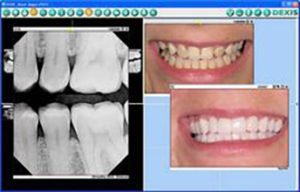

“I don’t think you can separate digital X-rays from digital camera images in their importance when relating with patients for the simplest of cosmetic procedures to comprehensive reconstruction. Both types are invaluable for patient education and case presentation.

Patients are amazed when I show them full-screen X-ray and camera images. Many have never taken a close look at their smiles, and so few have even seen their posterior teeth. I start with camera images, and then go directly to enlarged X-rays to discuss the internal aspects of their teeth.

I keep all my digital images in the same software, making it easy to show them to patients and to follow the history of a patient’s case. I can look at a case today and compare to 5 years ago, or anywhere in between, without rifling through charts (Fig. 5).”

Theodore C. Hadgis, DDS, Grosse Pointe Woods, MI